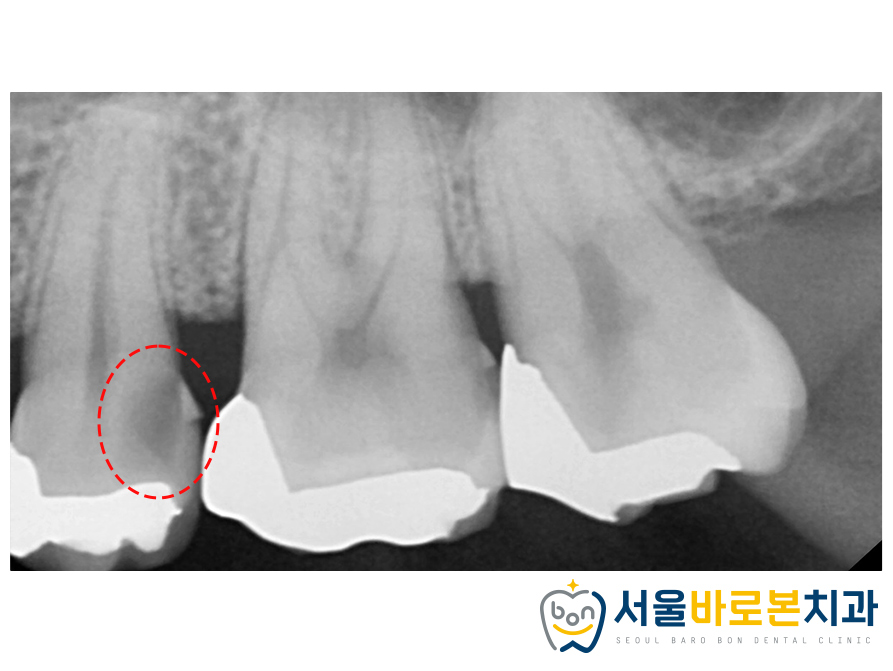

문제가 있는 부위를 조금 더

자세하게 확인하기 위해

치근단 사진을 촬영해 보았는데,

인레이 보철 하방으로

2차 충치가 생겨있는 것을

확연하게 체크할 수 있었습니다.

건강한 치아나 뼈가 있는 부분은

밀도가 높아 방사선이 투과하지 못해

하얗게 나온 것에 반면,

충치나 염증 등 좋지 않은 부위는

위와 같이 까맣게 나타나는데요.

충치가 치아 내부 조직인 신경까지 깊게 진행되어

환자분께서 통증의 불편감을 느끼고 계셨고,

신경치료 및 크라운 수복을 도와드리기로 했습니다.